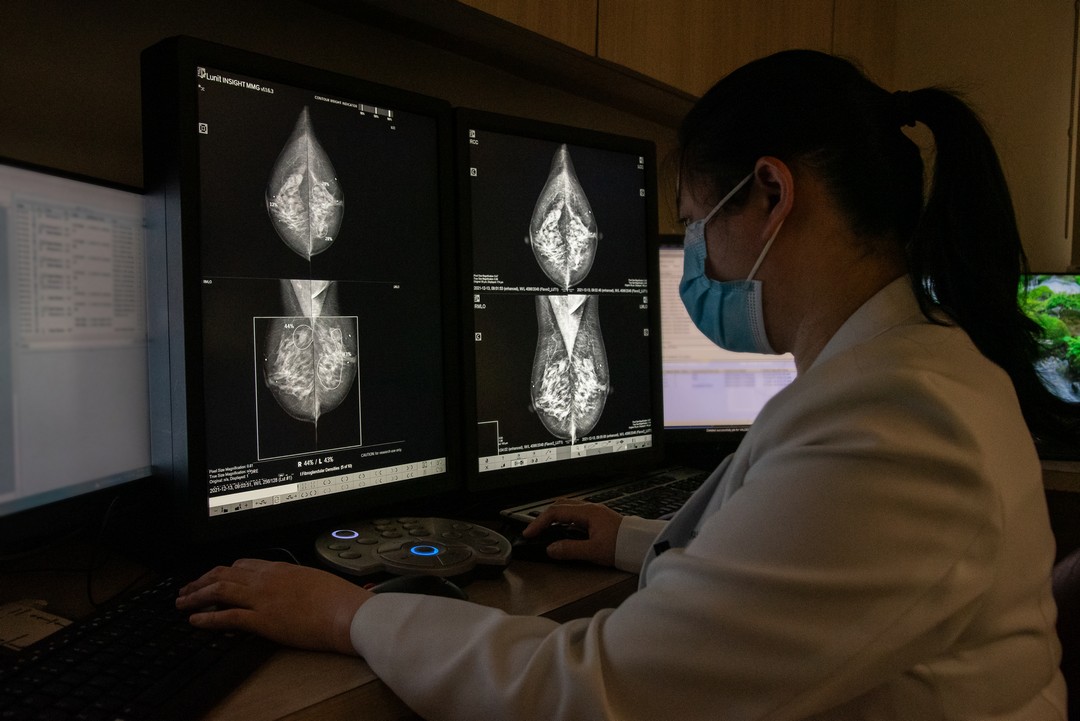

Looking forward, TMC plans to harness Artificial Intelligence (AI) to promote personalized healthcare, optimize its operations, and shift its focus from disease management to prevention. These initiatives aim to cement TMC’s position as a leading healthcare provider in the country.